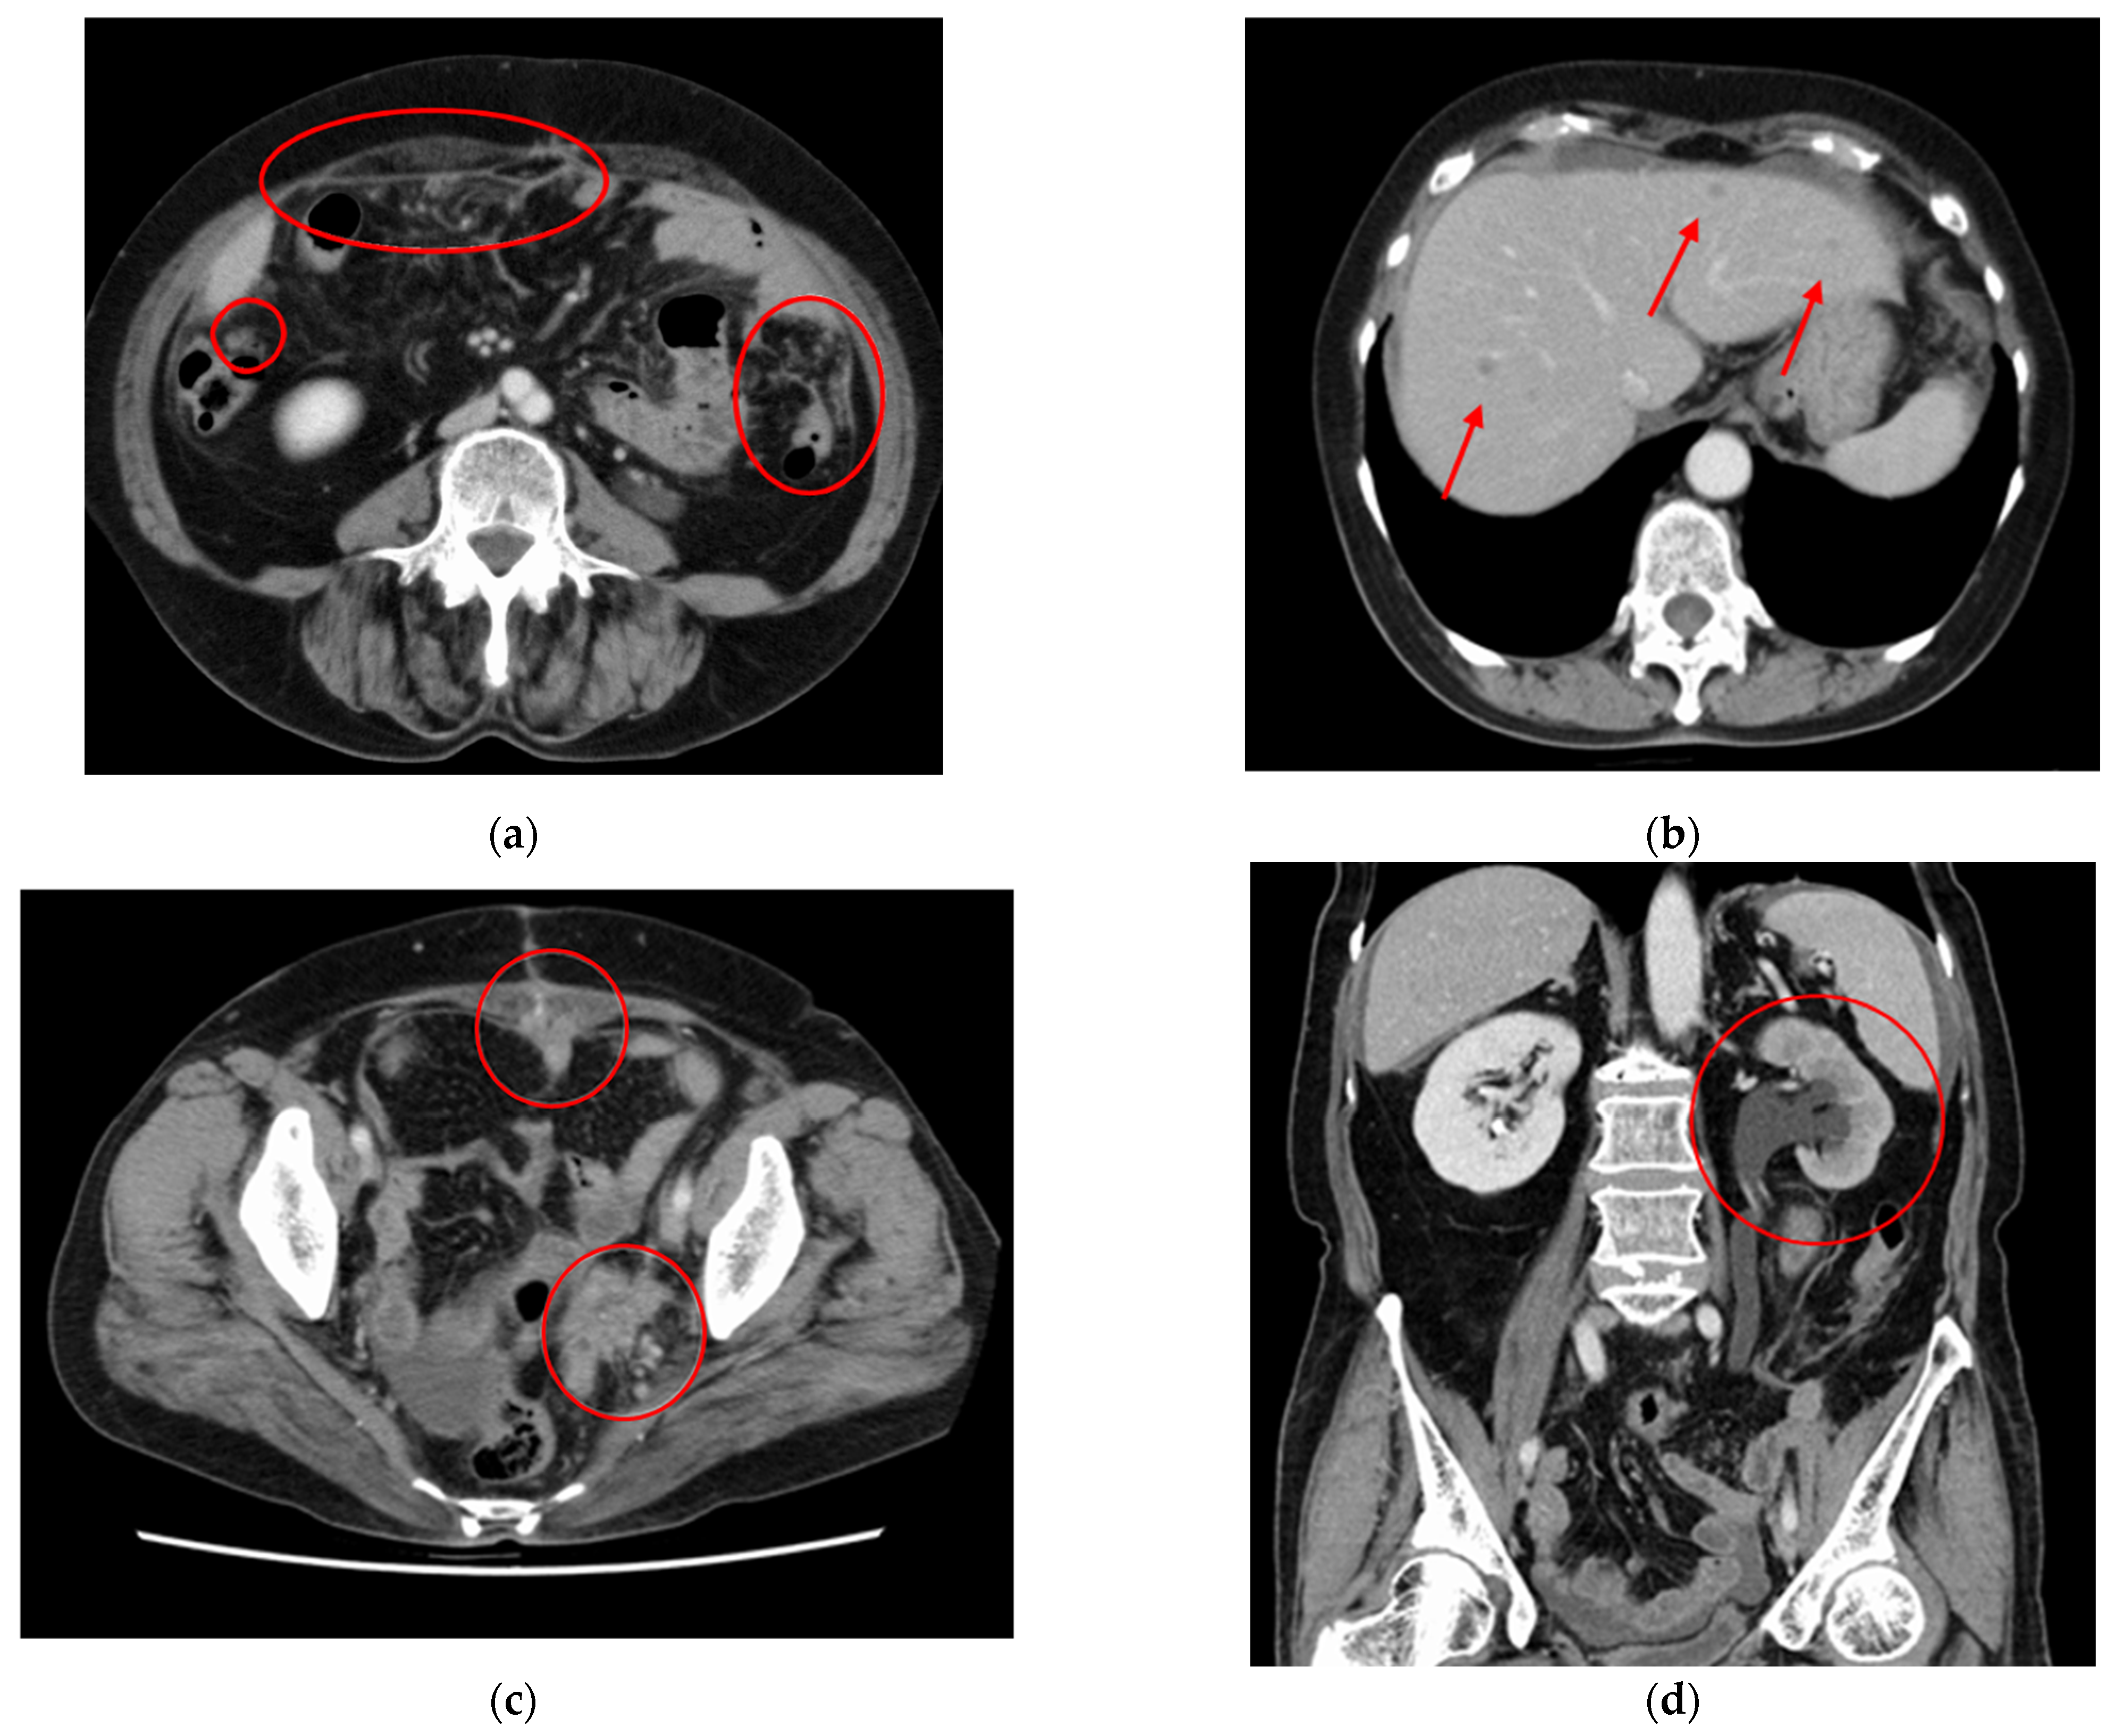

2. Case Presentation Section